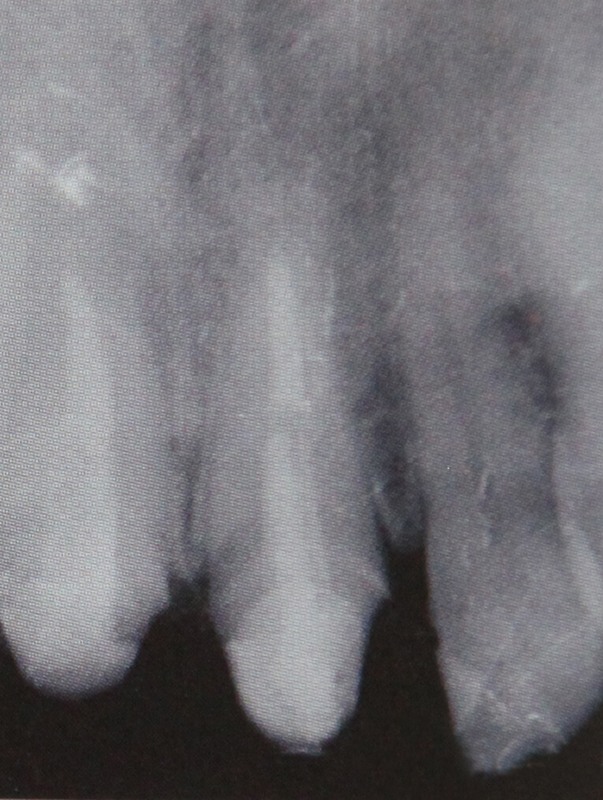

In fazele initiale caria dentara nu poate fi observata decat de medicul dentist, atunci cand caria este sesizata de pacient, leziunile sunt deja avansate. La inceput caria se manifesta ca o coloratie maronie la nivelul dintelui, ulterior apare o cavitate care continua sa se mareasca.

Specialitatea care se ocupa cu tratamentul canalelor radiculare reprezentand baza stomatologiei, deoarece durata de viata a dintelui depinde in primul rand de corectitudinea acestui tratament. Tratamentul de canal consta in indepartarea tesuturilor pulpare din canalele radiculare urmat apoi de curatarea largirea si obturarea lor.

Strategia acestor tratamente va fi deci de a evita sau de a elimina inflamatia tesuturilor periapicale care este provocata de fenomene microbiene si imunologice asociate a caror origine se gasesc in patologia endodontica. Obturatia de canal reprezinta ultima etapa a tratamentului si consta in sigilarea radacinilor cu materiale speciale. Durata tratamentului depinde de starea anterioara a nervului (inflamatii, infectii) dar si de dificultatea interventiei.